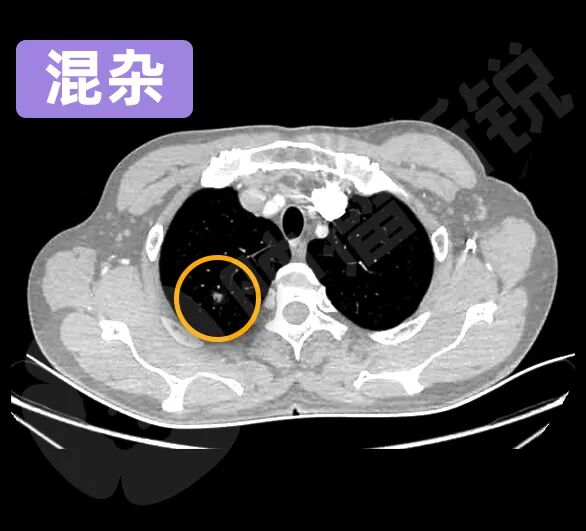

根据磨玻璃结节所包含的实性成分的不同,又可以分为纯GGO、混杂GGO、半实性GGO等不同亚型。

混杂GGO在影像上显示为云雾状伴有实性特征,就像一团棉絮。